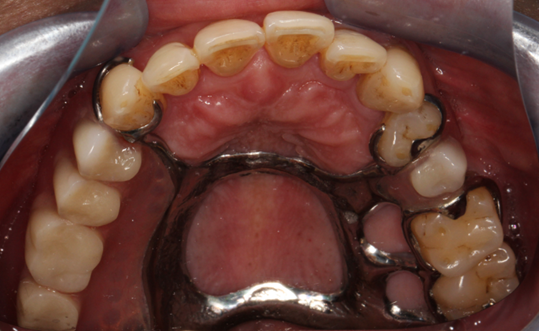

图片2.png

图2.口内佩戴的活动义齿